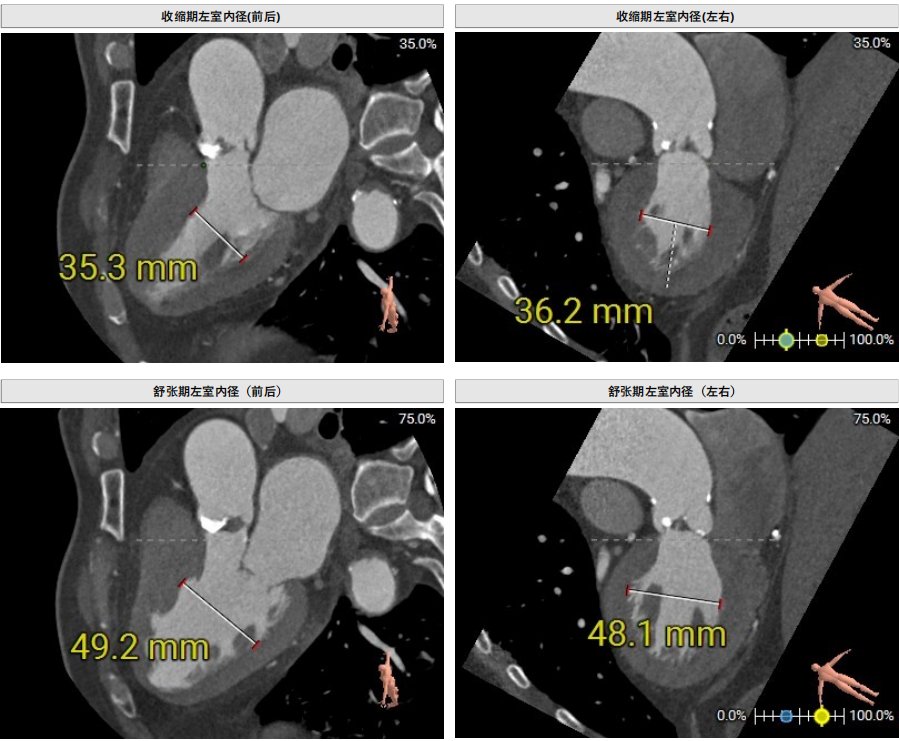

EDD42cm,EF64%

CT评估-左室测量:收缩期及舒张期左室内径可,舒张期瓣叶关闭良好